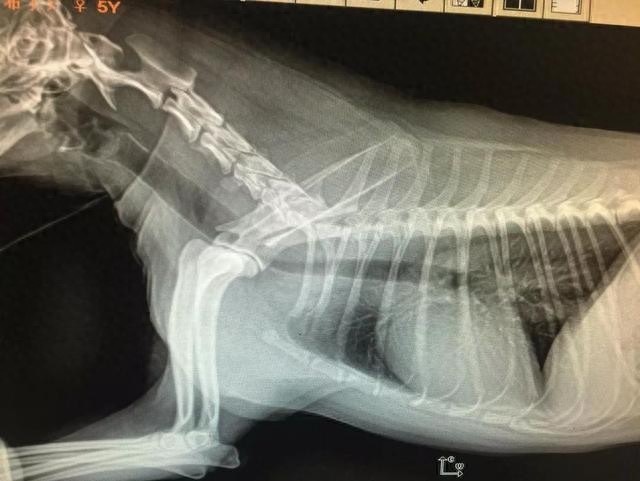

医生一般会进行心脏听诊,量血压,X光检查,有经济条件的主人还可以选择做心脏B超进一步确诊心脏病的病因是什么。

一般来说左心肥大二尖瓣关闭不全的话,医生会开强心药加强心肌收缩,利尿药,降低心脏四周血管压力的药。